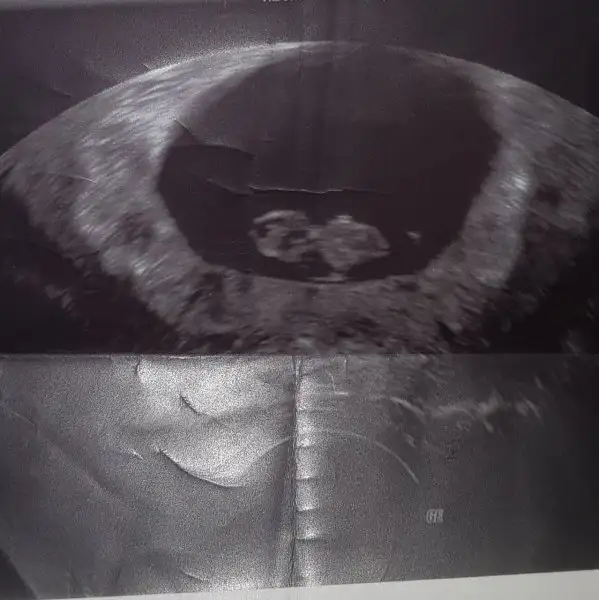

bebegin7-8 haftalıkkenki usg resimine direkt baktıgınızda;

bebek kesenin soluna yakınsa bebek erkek,

sagına yakınsa kız.